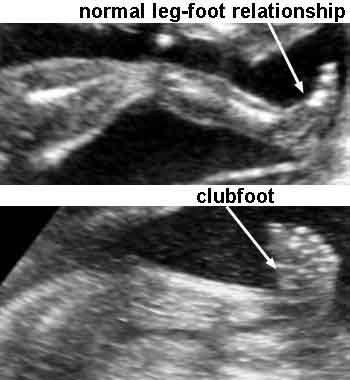

Talipes equinovarus

Talipes equinovarus

What is Talipes?

AKA Club foot.

front half of the foot turns inwards and downwards